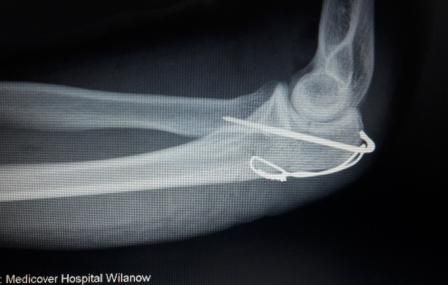

Dr hab. n. med. Ireneusz Babiak - ponad 30-letnie doświadczenie zawodowe zdobywane w trakcie pracy i szkoleń w szpitalach klinicznych w Polsce, Niemczech, Szwajcarii i Szwecji. Specjalizuje się w diagnostyce i leczeniu chorób stawów kolanowych, biodrowych, barkowych, kręgosłupa, deformacji stopy, terapii podciśnieniowej ran (tj NPWT) systemami VAC, Pico, Avelle. Wykonuje operacje: endoprotezy stawu biodrowego i kolanowego ( w ostatnim roku 200 endoprotez implantowanych osobiście i asysta do kolejnych 200 endoprotez), zespół cieśni nadgarstka, palec zatrzaskujący, paluchy koślawe (haluxy), palce młotkowate, zespolenia złamań kości, zaburzenia zrostu, operacje rewizyjne endoprotez stawów, operacyjne leczenie zapaleń kości stawów z zastosowaniem biomateriałów, przeszczepy skóry. Do roku 2017 adiunkt oraz ordynator Oddziału IV w Klinice Ortopedii Traumatologii Warszawskiego Uniwersytetu Medycznego (WUM), oraz wykładowca na English Division Medical University of Warsaw. W roku 2018 stanowisko överläkare - specjalista odpowiedzialny za endoprotezoplastykę biodra i kolana w Klinice Ortopedii w Eskilstunie w Szwecji. Wykładowca na kursach szkoleniowych z operacji rewizyjnych endoprotez stawów, zapaleń kości i stawów, planowania w endoprotezoplastyce stawów, powikłań w ortopedii. Członek towarzystw naukowych: PTOiTr (Polskie Towarzystwo Ortopedyczne i Traumatologiczne), EBJIS (European Bone and Joint Infection Society), PTZS (Polskie Towarzystwo Zakażeń Szpitalnych).

Zdjęcia i filmy